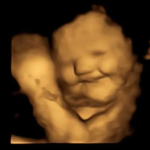

Comportamento fetal - 24/09/2022 às 15:03

Fetos alteram expressão facial a partir de gosto dos alimentos, diz estudo

Durante a pesquisa, os fetos faziam "cara de riso" no útero quando suas mães consumiam cenoura, e "cara de choro" quando elas comiam couve